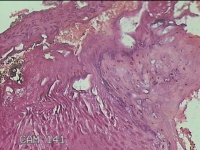

外阴赘生物

性别

女

年龄

33岁

临床诊断

外阴尖锐湿疣

一般病史

发现外阴尖锐湿疣4个月。

标本名称

大体所见

灰白暗红色不规则碎组织0.3x0.2x0.1cm一堆。

良性病变,考虑湿疣。